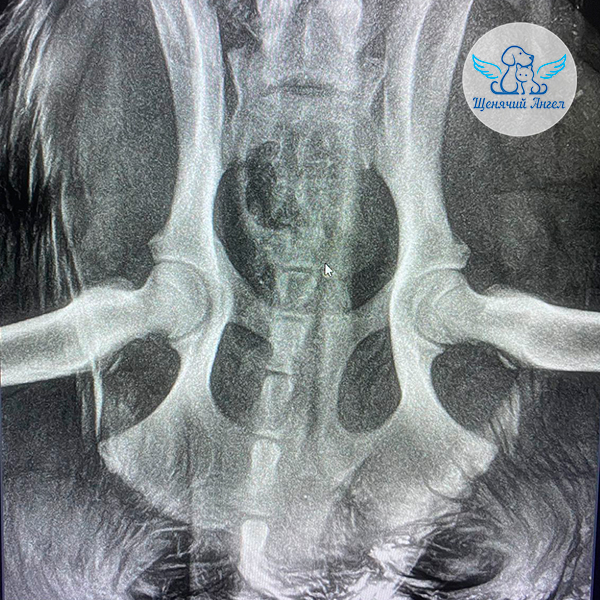

🕊 Друзья, делимся новостями о щенке Севере, которого сбили на дороге в селе рядом с Буйнакском 🚗💔.

Благодаря вашей помощи Севера удалось экстренно госпитализировать в местную ветеринарную клинику 🏥, где ему провели инфузионную терапию и сняли выраженный болевой синдром 😖, из-за которого щенок был практически полностью обездвижен. После стабилизации состояния Севера мы перевезли в Москву, в ветеринарный центр «Юна» для дальнейшей диагностики 🧫🔬.

📋 В клинике щенку выполнили все необходимые обследования: сдали анализы, сделали УЗИ и рентген 🩻 . К счастью, серьёзных патологий не выявлено 🙏🏻. Однако у него сохраняются трудности с опорой на задние лапы 🐾.

Для уточнения причины Севера осмотрел ортопед 👨🏻⚕, но осмотр оказался затруднён из-за выраженной стрессовой реакции и агрессии при манипуляциях 😔.

Также у щенка на бедре выявлен участок гиперемии, похожий на начинающийся пролежень. Все повреждения обработаны и находятся под контролем врачей 👩🏼⚕.

На данный момент наша основная задача – дождаться снижения уровня стресса у Севера и стабилизации его поведения. Это позволит провести полноценное дополнительное обследование и уточнить дальнейший план лечения ❤🩹.

Огромное спасибо каждому из вас за поддержку, участие и добро, которое помогло спасти Северу жизнь 🫶🏻. Вместе мы делаем всё возможное, чтобы малыш как можно скорее вернулся к нормальной жизни без боли и страха 🐶🍀.